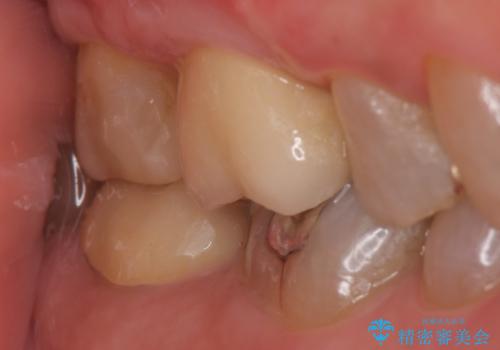

オールセラミッククラウン・セラミックインレー 歯茎より深い虫歯の治療

その後歯茎の回復を待ち、オールセラミッククラウンおよびセラミックインレーによる補綴・修復を行いました。

セラミックインレーについて

当院のセラミックインレーはemaxという強度と審美性に優れた材料を使用しています。

またプレス方式でインレーを製作しているため、削り出しで製作するCADCAMより優れた適合性も持ち合わせており、虫歯が再発しにくい修復物です。